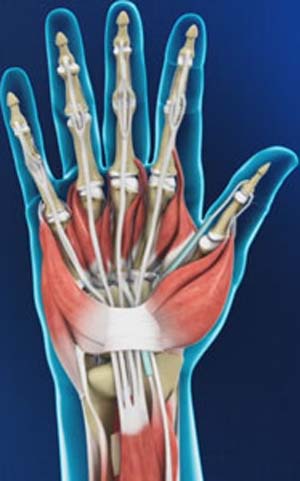

Hand and Wrist Anatomy

The human hand is made up of the wrist, palm, and fingers and consists of 27 bones, 27 joints, 34 muscles, over 100 ligaments and tendons, and many blood vessels and nerves.